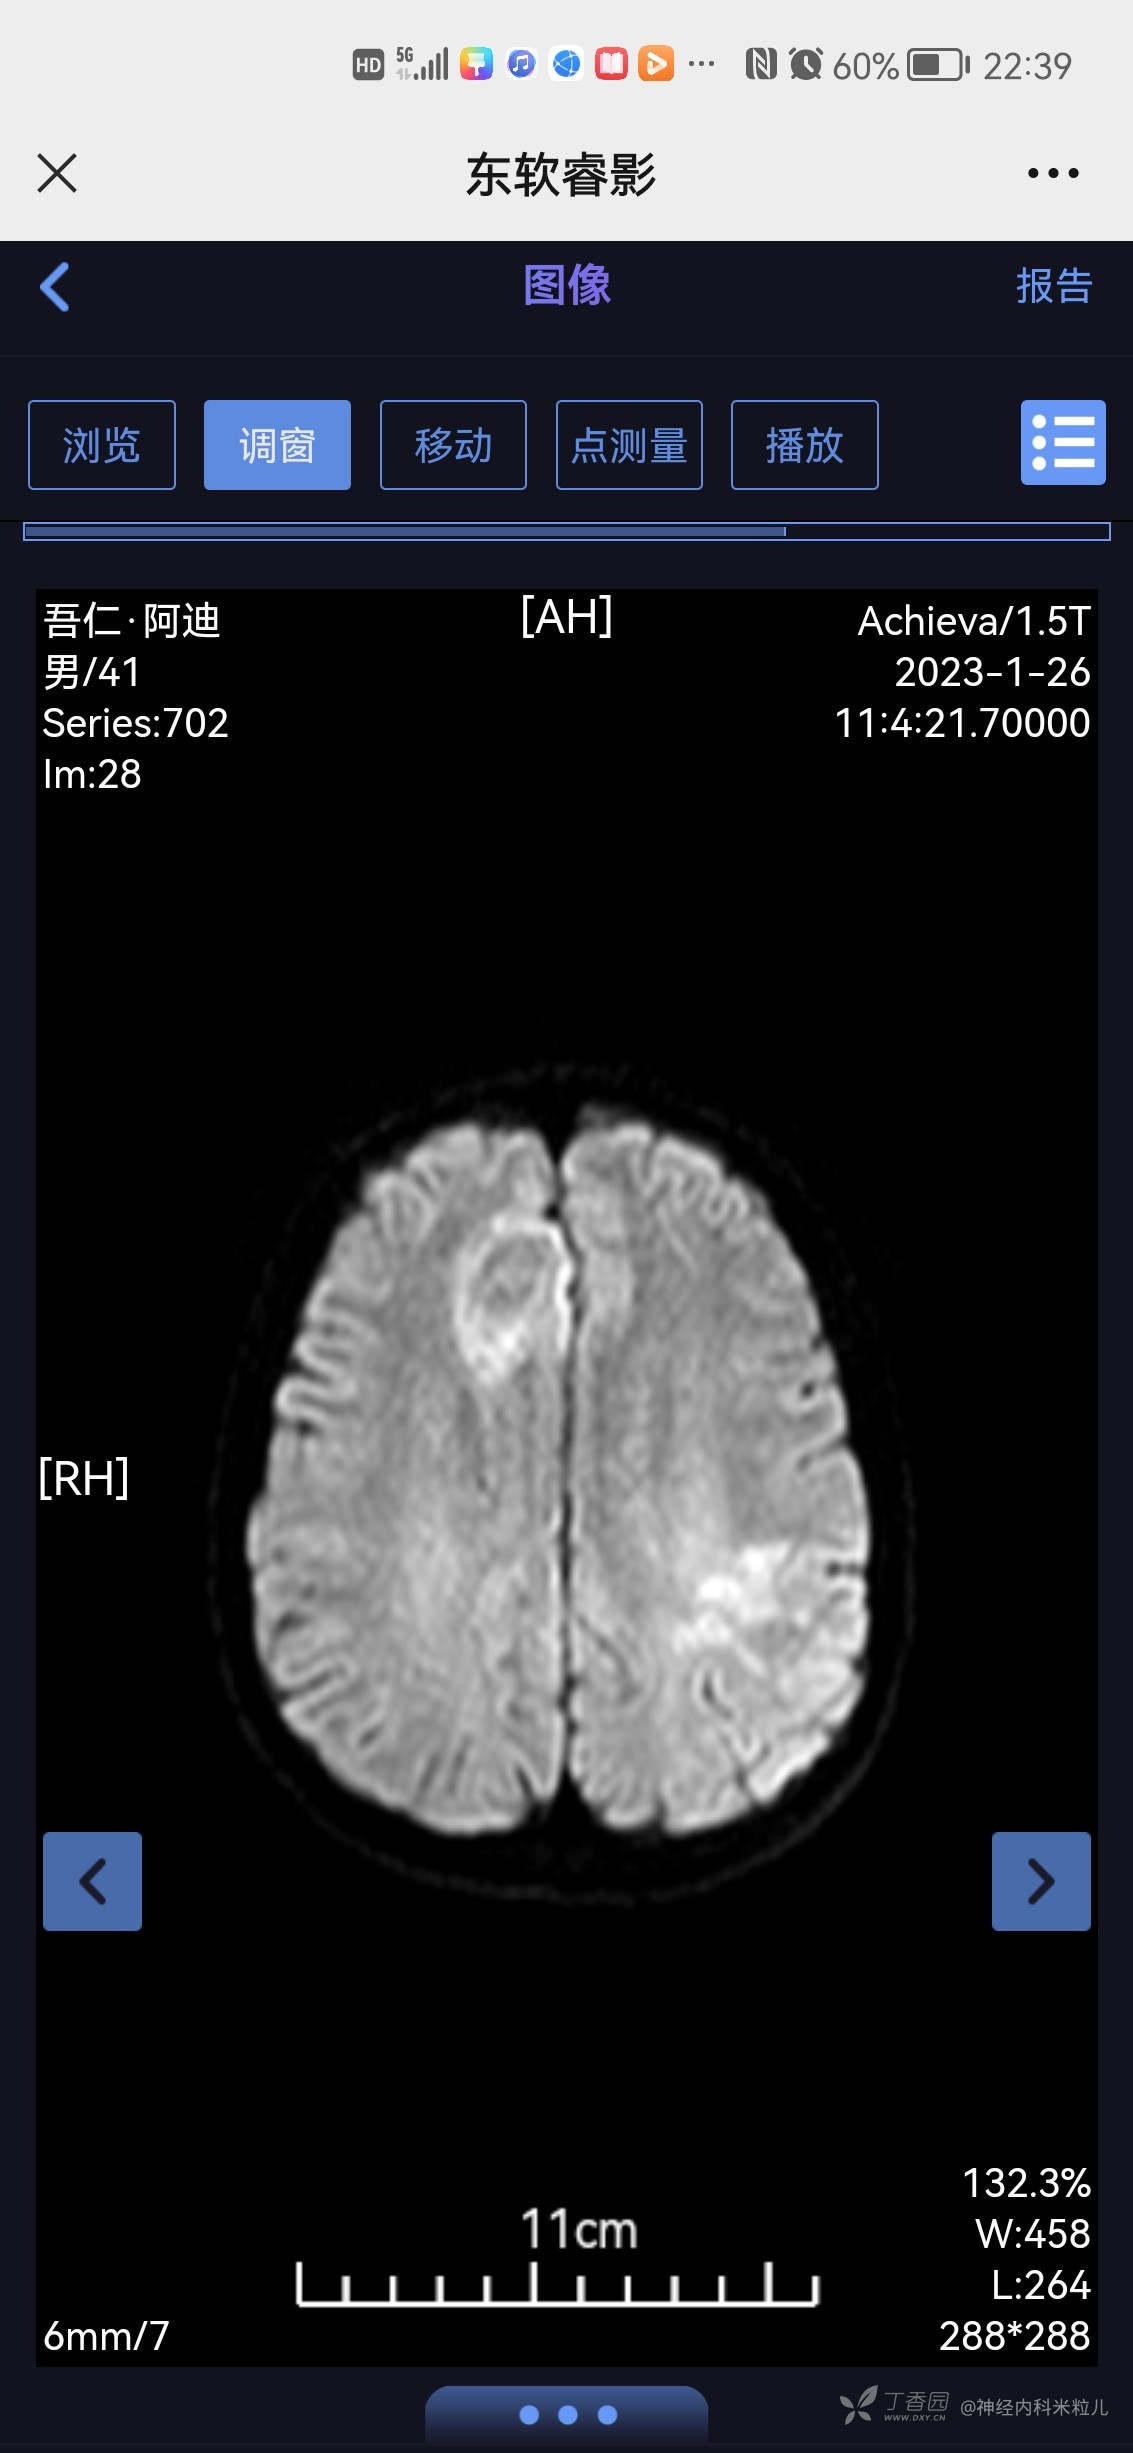

青鹊词等 3人推荐患者家属及本人共诉:于1月6日左右突然出现头痛,呈间断搏动性疼痛,以额部疼痛为主,休息后略好转,白天头痛明显,夜间尚可,并伴有发热,未测体温,发热3天,呈持续发热,并伴有腹泻2天,呈水样便,每日7-8次,无黑便、无血便。就诊当地镇医院,具体诊断及治疗不详,随后症状自行改善,13日患者因手抖,心悸不适来我院内分泌住院治疗诊断甲亢,并给于相应治疗:甲巰咪唑30mg一日次口服,利法沙班15mg一日一次口服,普萘洛尔10mg一日三次口服,查2023年1月18日我院头颅核磁提示:颅内多发异常信号,考虑:感染性病变,建议增强检查。随后患者出院,头痛未再次发作,故今日为进一步查明病因来我院,门诊以“颅内感染、甲亢”收住我科,病程中患者有发热,有头痛、无头晕、无恶心、呕吐、无乏力、有多汗、有心悸、无心前区疼痛、无腹泻,无黑便、无脓血便、饮食睡眠可,近期有体重下降,具体不详。

2023年1月18日我院头颅核磁提示:颅内多发异常信号,考虑:感染性病变,建议增强检查。}